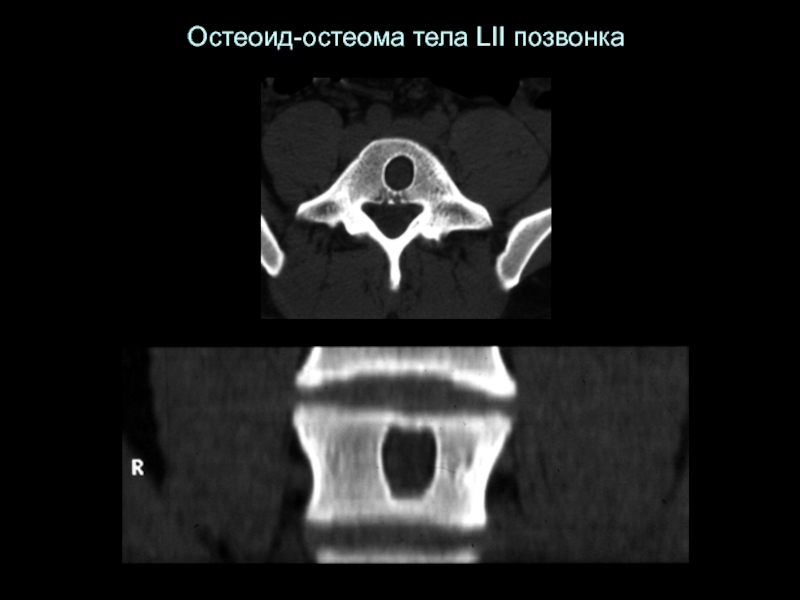

Слайд 26Остеоид-остеома тела LII позвонка

Остеоид-остеома тела LII позвонка